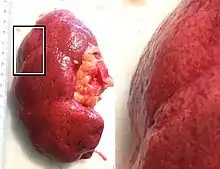

In the kidneys, as a result of benign arterial hypertension, hyaline (pink, amorphous, homogeneous material) accumulates in the walls of small arteries and arterioles, producing the thickening of their walls and the narrowing of the arterial openings, a process known as arteriolosclerosis. The resulting inadequate blood flow produces tubular atrophy, interstitial fibrosis, and glomerular alterations (smaller glomeruli with different degrees of hyalinization – from mild to sclerosis of glomeruli) and scarring around the glomeruli (periglomerular fibrosis). In advanced stages, kidney failure will occur. Functional nephrons[6] have dilated tubules, often with hyaline casts in the opening of the tubules. Additional complications often associated with hypertensive nephropathy include glomerular damage resulting in protein and blood in the urine.

In benign nephrosclerosis, the changes occurring are gradual and progressive, however, there can be sufficient kidney reserve capacity to maintain adequate kidney function for many years.[10] The large renal arteries exhibit intimal thickening, medial hypertrophy, duplication of the elastic layer. The changes in small arterioles include hyaline arteriolosclerosis (deposition of hyaline, collagenous material), which causes glomerular collapse (wrinkling and thickening of capillary basement membranes and collapse of capillary lumen) and solidification (glomeruli exhibit sclerosis and increase in mesangial matrix). The degree of scarring correlates with the degree of glomerular filtration deficit.

Malignant nephrosclerosis is where hypertensive nephrosclerosis occurs in presence of malignant hypertension (when DBP > 130mmHg).[11] Vessels feature intimal thickening, fibrinoid necrosis, red blood cell fragmentation, extravasation, thrombosis. These changes create an exaggerated layered appearance (onion skinning).[12]